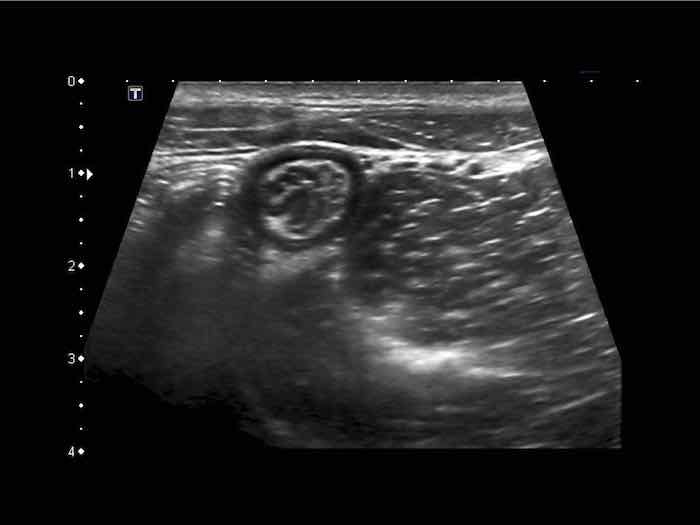

Đây là hình ảnh siêu âm của một trẻ 2 tuổi bị lồng ruột hồi manh tràng từng đợt, được khám trong khoảng thời gian giữa các cơn.

Hồi tràng với nhiều mảng Peyer sa vào manh tràng.

Hình ảnh siêu âm kinh điển của lồng ruột hồi-manh tràng ở hai trẻ khác nhau.

Trong cả hai trường hợp, đoạn hồi tràng bị lồng được định vị không đối xứng bên trong ống lồng ngoài, do mạc treo ruột tăng âm có chứa mỡ, bám vào hồi tràng và đi theo hồi tràng khi bị kéo vào trong.

Trong mạc treo, siêu âm cho thấy một hạch bạch huyết mạc treo (hbh) phóng đại ở cả hai.

Các hạch này phì đại như một phần của tình trạng tăng sản hạch bạch huyết toàn thân và khônghu trú trong lòng hồi tràng.

Do đó đây không phải là điểm dẫn đầu nguyên phát. Ở bệnh nhân bên phải, ruột thừa (mũi tên) cũng bị kéo vào trong.

Lưu ý cấu trúc đa lớp của thành bụng phía trước của phức hợp lồng ruột, đại diện cho ba lớp thành ruột bị gấp lại.